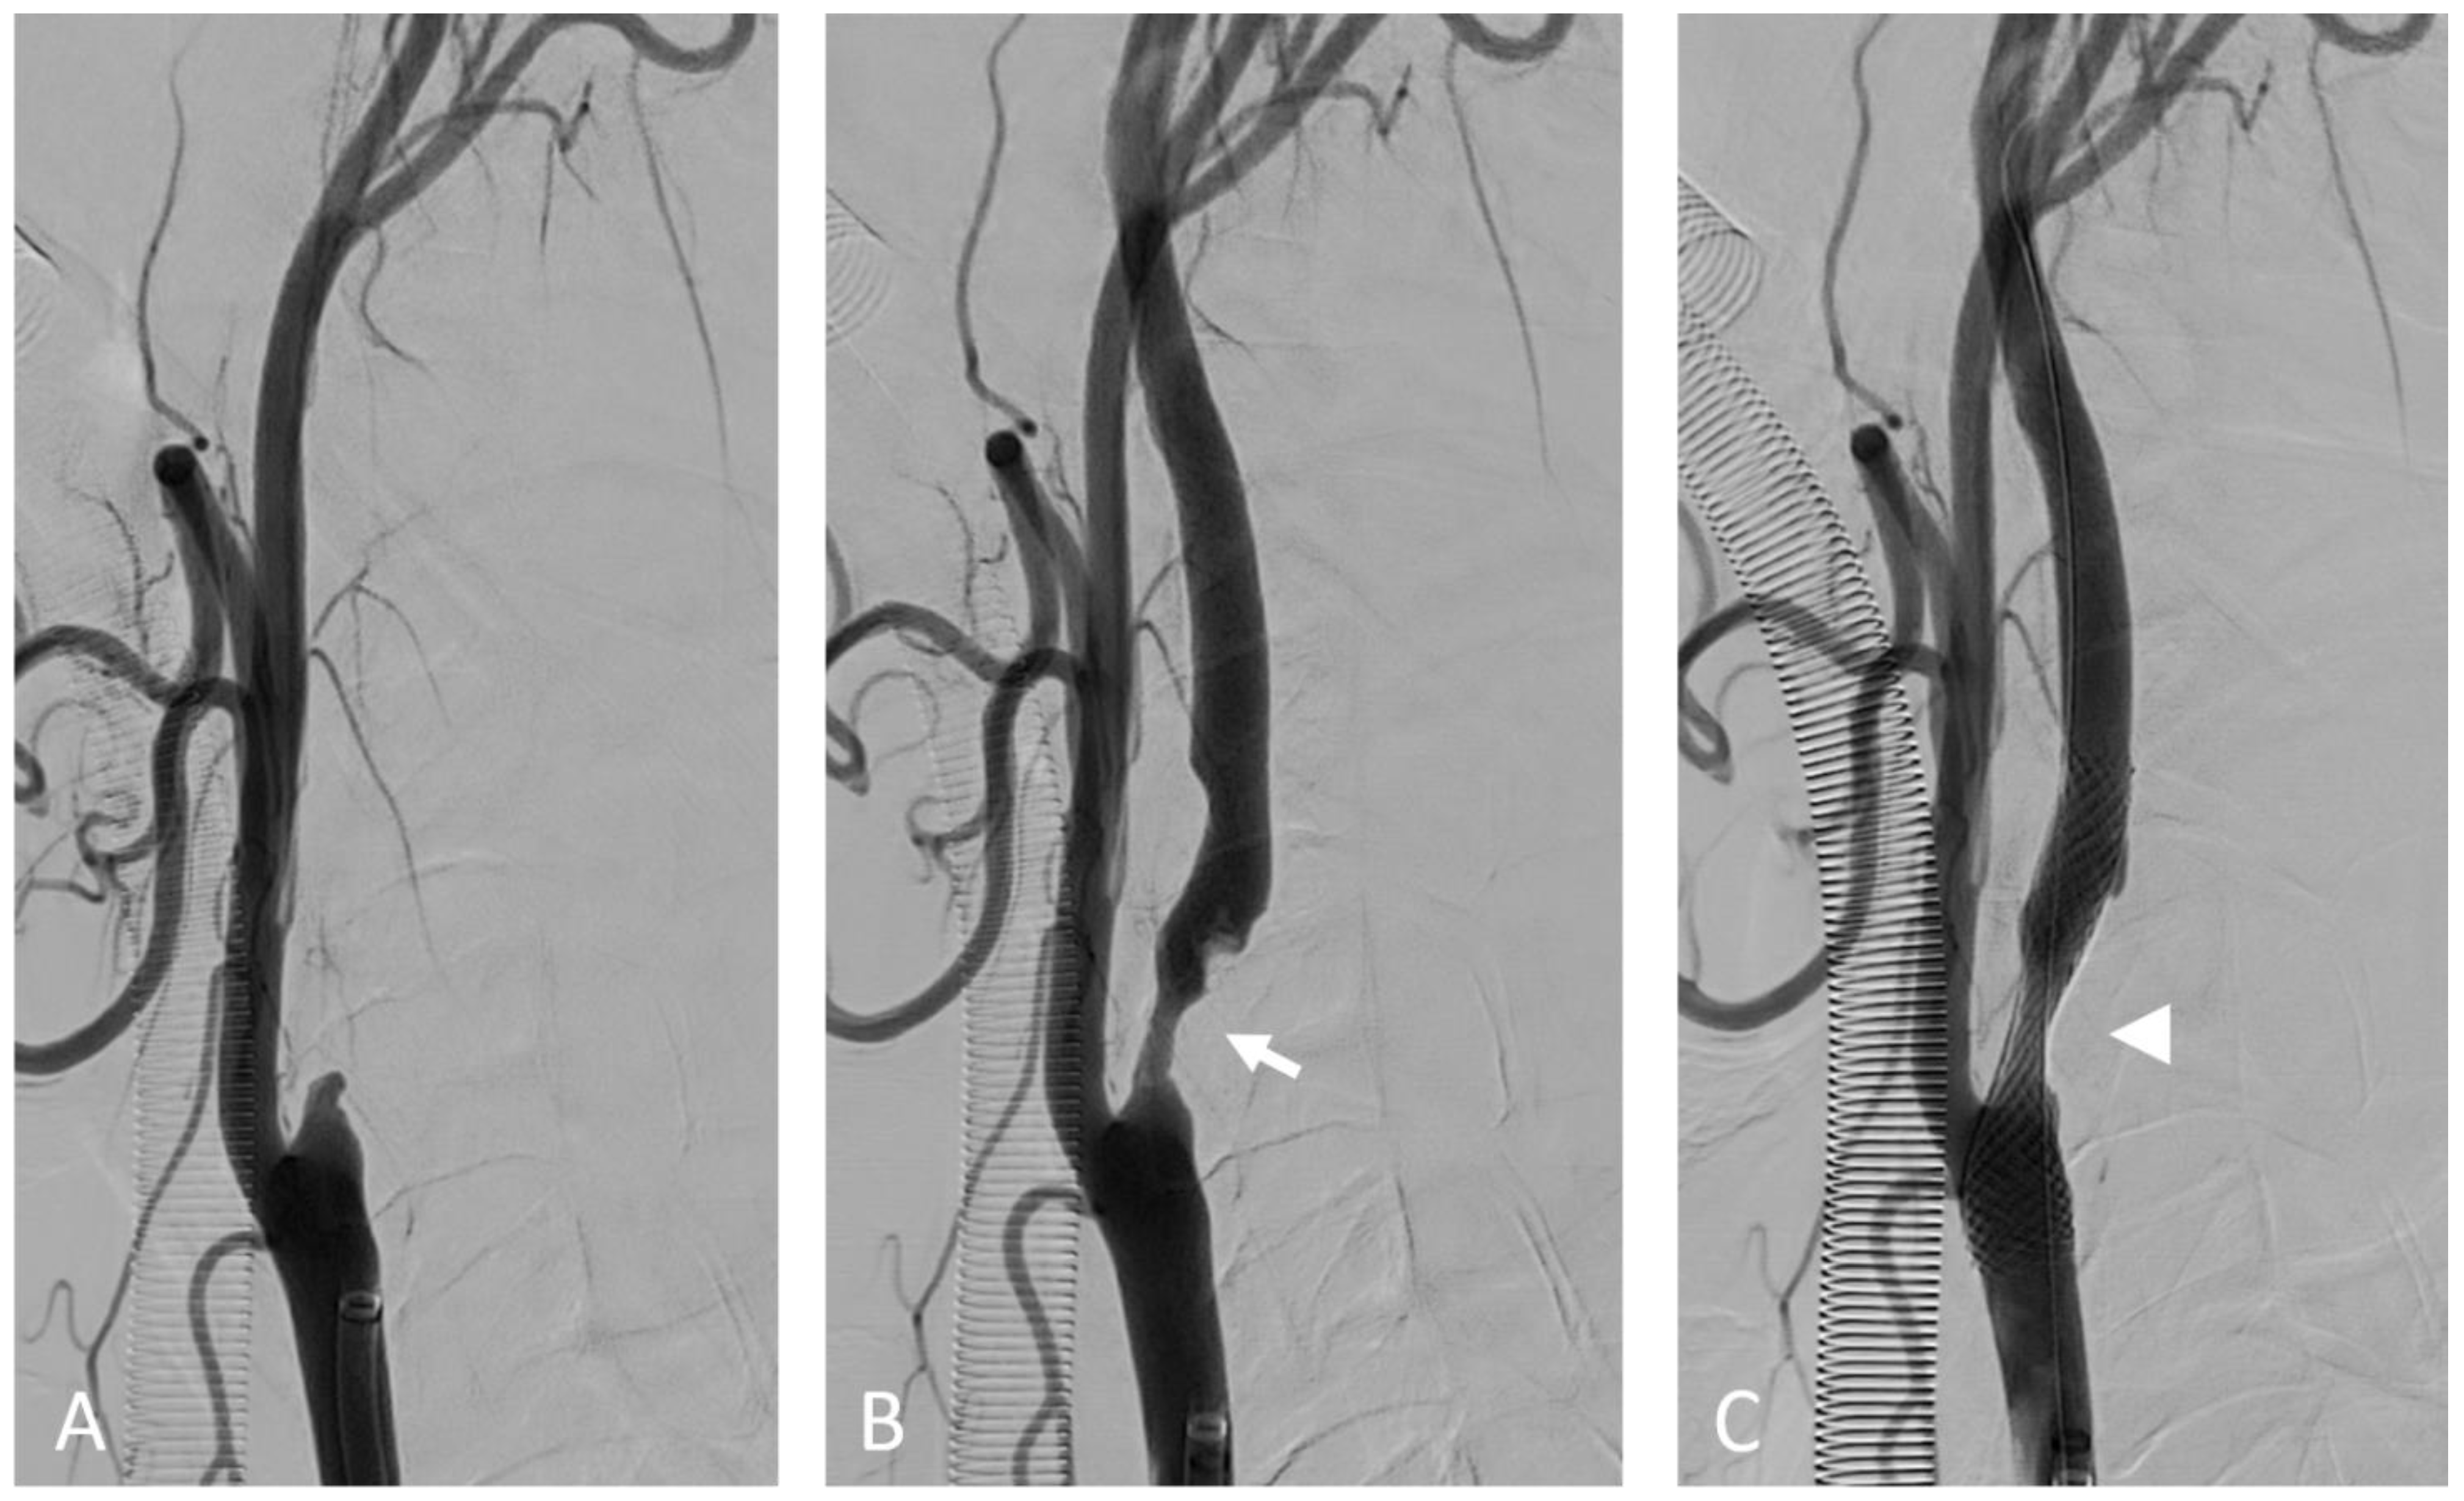

- Partida, R.A.; Libby, P.; Crea, F.; Jang, I.-K. Plaque erosion: A new in vivo diagnosis and a potential major shift in the management of patients with acute coronary syndromes. Eur. Heart J. 2018, 39, 2070–2076. [Google Scholar] [CrossRef]